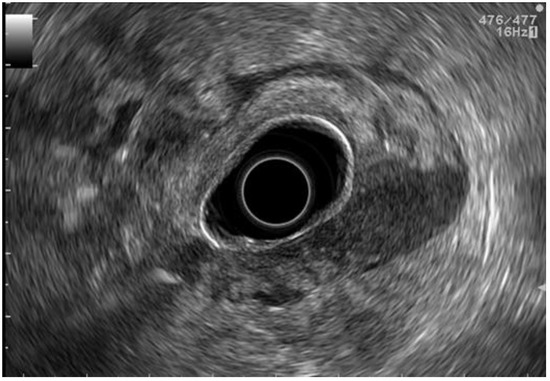

2.3. EUS Staging